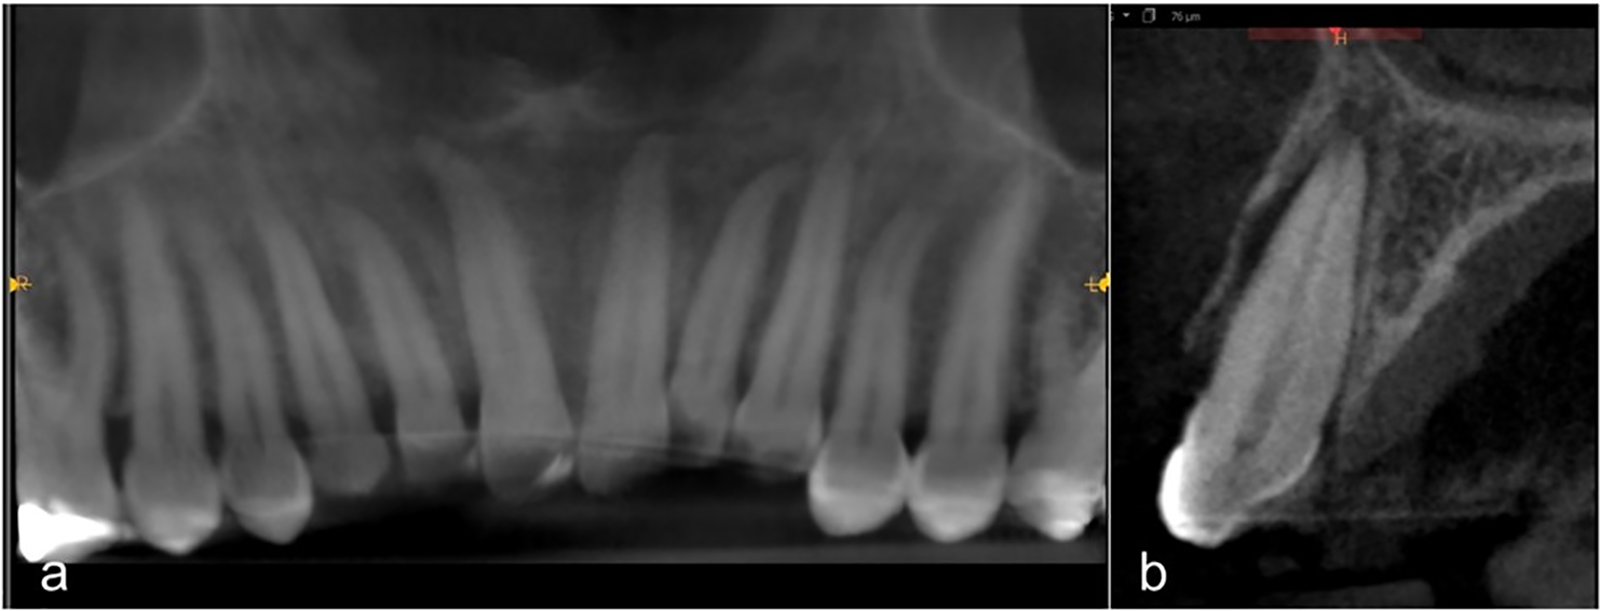

Over 50 days, new CBCT images were performed to monitor the fractures, verifying proper bone healing and dental alignment. The five traumatized teeth showed no mobility or ankylosis. Bone healing of the fractures and dental alignment are observed in panoramic view (Fig. 6a). Sagittal section of the left canine shows healing of the triple fracture of the buccal bone wall and preserved periodontal ligament space (Fig. 6b).

Fig. 6. CBCT follow-up at 50 days.

At 16 months, the third CBCT examination was performed, to compare the sagittal sections and observe the progress. The sagittal CBCT of the right central incisor at 48 hours showed lateral dislocation and fracture of the incisal third of the crown, a wide periapical free space (PC) due to the nasal fossa floor fracture, normal width of the buccal bone wall (BW), and a control pulp chamber and pulp canal (PCO) diameter without calcifications (Fig. 8a).

Fig. 8. Evolution of the right central incisor: a) sagittal CBCT at 48 hours, b) control at 16 months.

The 16-month follow-up showed a reduction in the PC and BW following bone healing and maintenance of the incisal third reconstruction. Furthermore, confirming pulp canal obliteration (PCO) in the maxillary right central incisor, which had reduced its diameter by more than 60% in the measurement taken at the widest area (junction of the middle third and the apical third of the root). The thin buccal bone wall reduced its width by 50% following bone remodeling (Fig. 8b). Although pulp vitality was preserved, a 5-year follow-up of all traumatized elements will be performed.